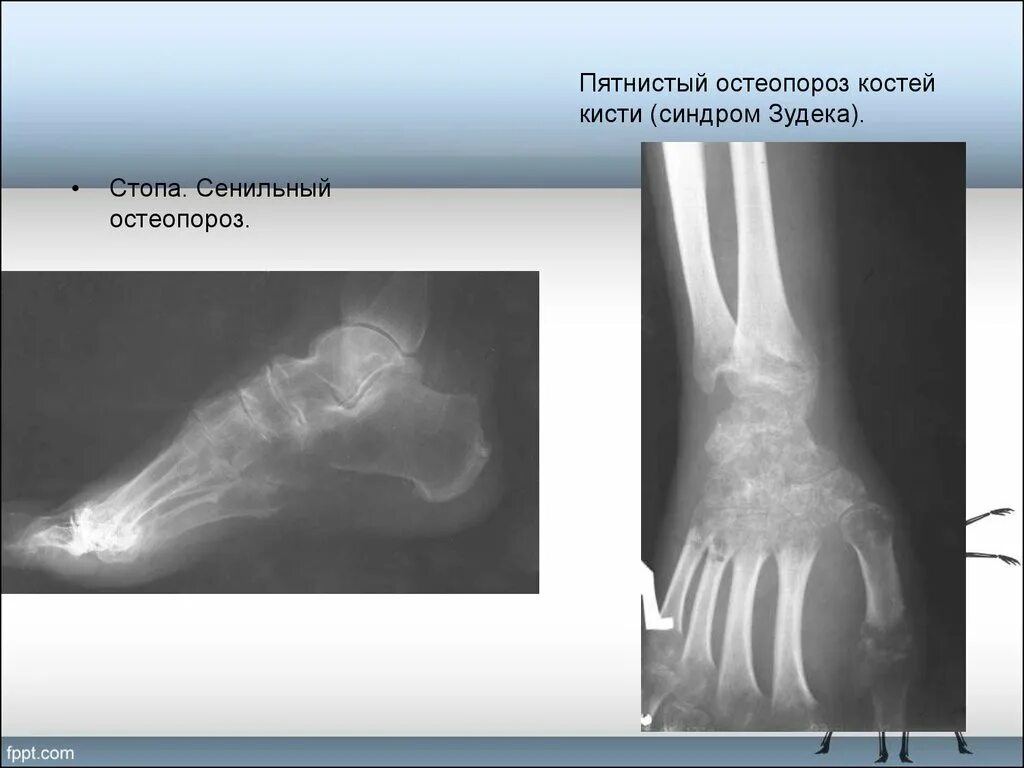

Изменения костной структуры